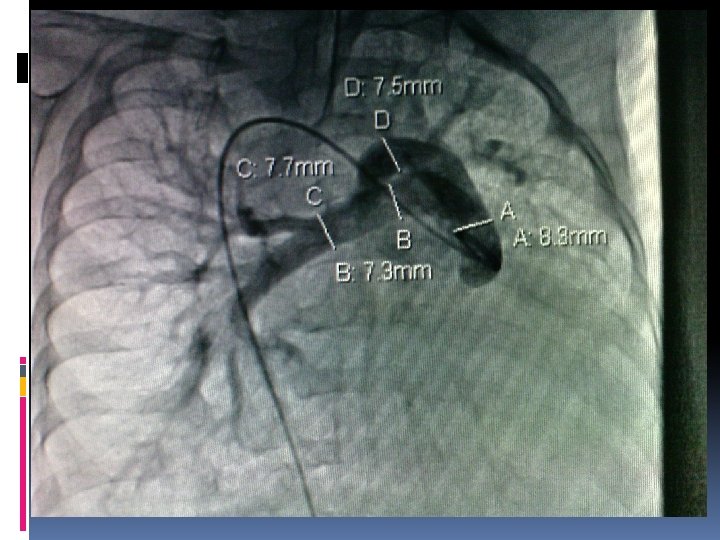

Completion of TCPC Surgical technique: How I do it? On CPB or Off-pump Dissection of IVC and PA Tailoring the PTFE conduit (at least size 16 mm should be selected for adequate IVC flow) Anastomosis: the IVC anastomosis is done first. Side-to-side fenestration